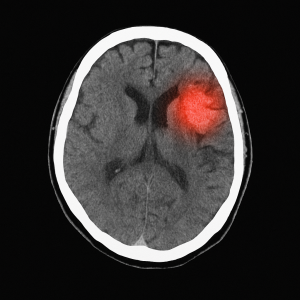

A stroke occurs when the blood flow to the brain is interrupted, either by a clot (ischemic stroke) or by bleeding (hemorrhagic stroke). This event prevents brain cells from receiving oxygen and nutrients, causing them to die within minutes.

In case of any suspicion, you should go to the emergency room immediately. Imaging tests such as CT scans or MRI help confirm the diagnosis. Treatment will depend on the type of stroke but may include: